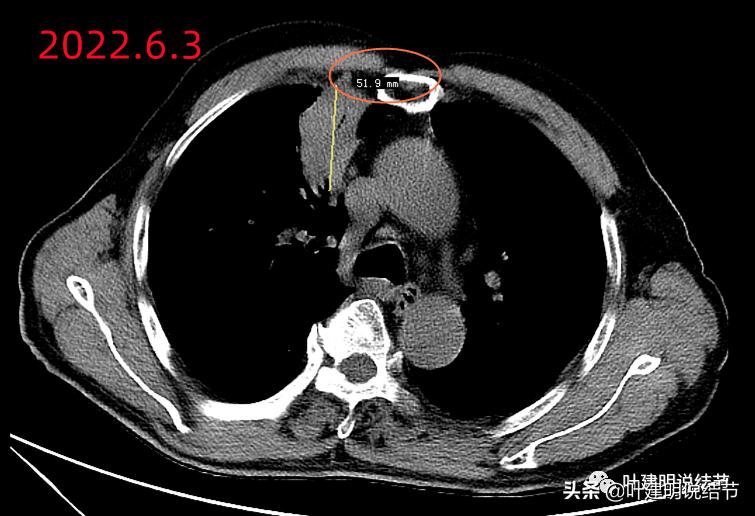

某A,男性,今年71岁,前些天因咳嗽痰血5天当地医院检查后发现右肺巨大占位考虑肺癌,遂找到我收住入院。我一看这么大一个肿块,有6厘米多,还有咳嗽与痰中带血,总基本上要考虑肺癌呀!予以完善相关术前检查准备手术治疗。但等其相关化验出来,发现肿瘤筛查指标都是基本正常的。我们同组的费苏鹏医生查房时提醒说“这么大的肿块,居然肿瘤指标都正常,会不会不是恶性的?”。我们与老谭一起一商量,也觉得有道理。所以与家属沟通后暂缓手术,先穿刺活检下。我们从他的影像开始先来看看:

纵隔窗见肿块巨大,内部密度略不均